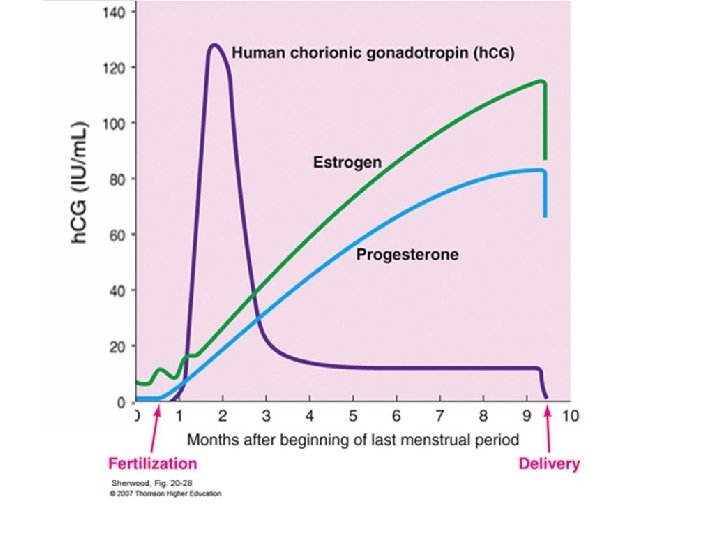

TVS “Milestones” Versus βh. CG m. IU/m. L Weeks Detection Level >5 3 -4 Choriodecidual thickening 100 Gestational sac (D Zone) 1000 -1500 Yolk sac Heart motion 7000 4 4 -5 5 - 6 10, 000 6 Embryonic Movem. > 10. 000 6 - 7 Maximum level 50, 000 to 100, 000 8 -10